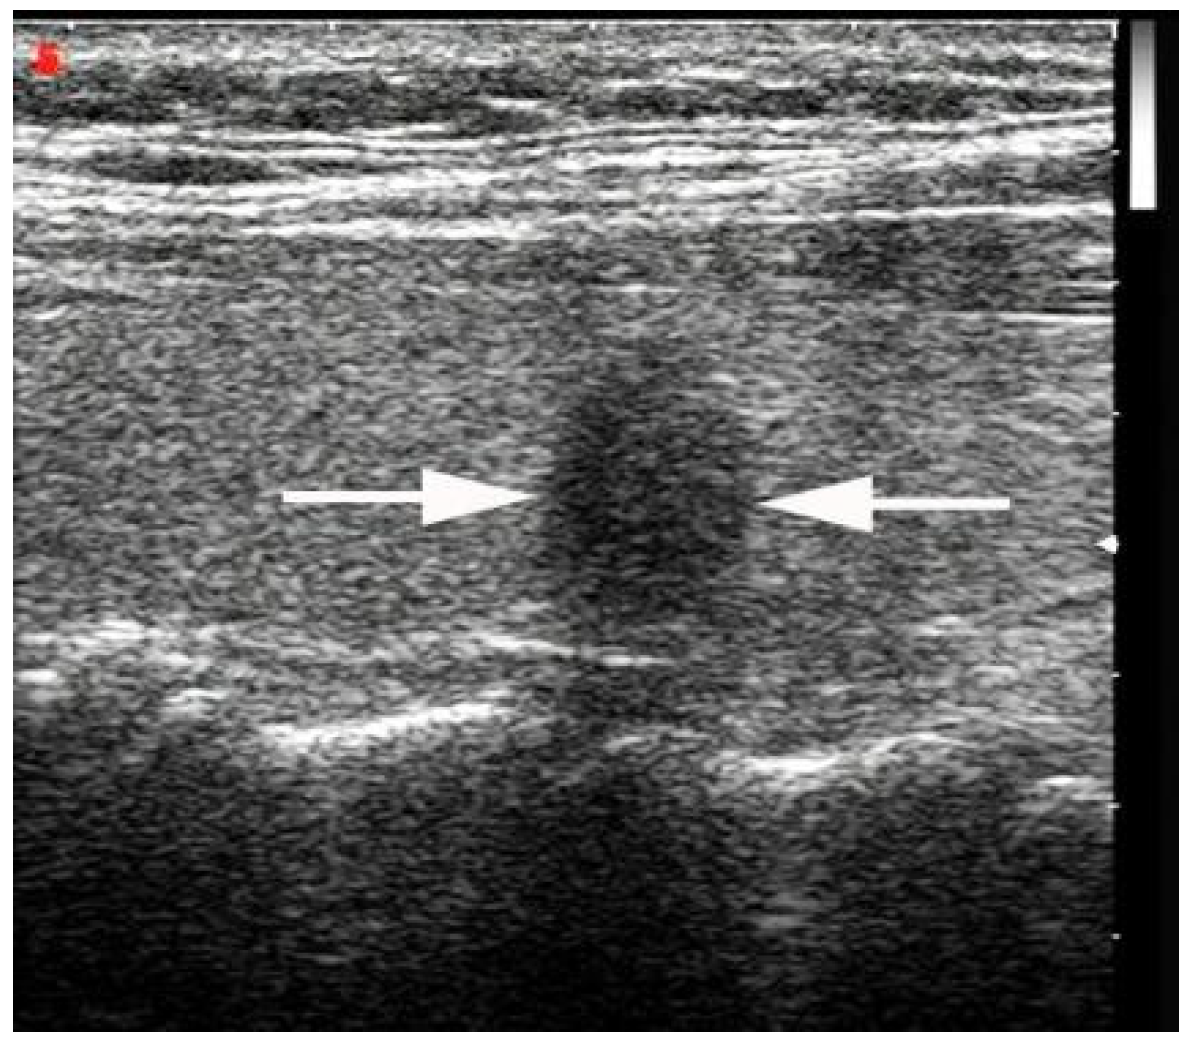

2.2. Ultrasound Imaging

- Chen, S.-P.; Hu, Y.-P.; Chen, B. Taller-Than-Wide Sign for Predicting Thyroid Microcarcinoma: Comparison and Combination of Two Ultrasonographic Planes. Ultrasound Med. Biol. 2014, 40, 2004–2011. [Google Scholar] [CrossRef]

- Kwak, J.Y.; Kim, E.-K.; Youk, J.H.; Kim, M.J.; Son, E.J.; Choi, S.H.; Oh, K.K. Extrathyroid Extension of Well-Differentiated Papillary Thyroid Microcarcinoma on US. Thyroid 2008, 18, 609–614. [Google Scholar] [CrossRef]

- Moon, S.J.; Kim, D.W.; Kim, S.J.; Ha, T.K.; Park, H.K.; Jung, S.J. Ultrasound assessment of degrees of extrathyroidal extension in papillary thyroid microcarcinoma. Endocr Pract. 2014, 20, 1037–1043. [Google Scholar] [CrossRef]

- Chung, S.R.; Baek, J.H.; Choi, Y.J.; Sung, T.Y.; Song, D.E.; Kim, T.Y.; Lee, J.H. Sonographic Assessment of the Extent of Extrathyroidal Extension in Thyroid Cancer. Korean J. Radiol. 2020, 21, 1187–1195. [Google Scholar] [CrossRef]